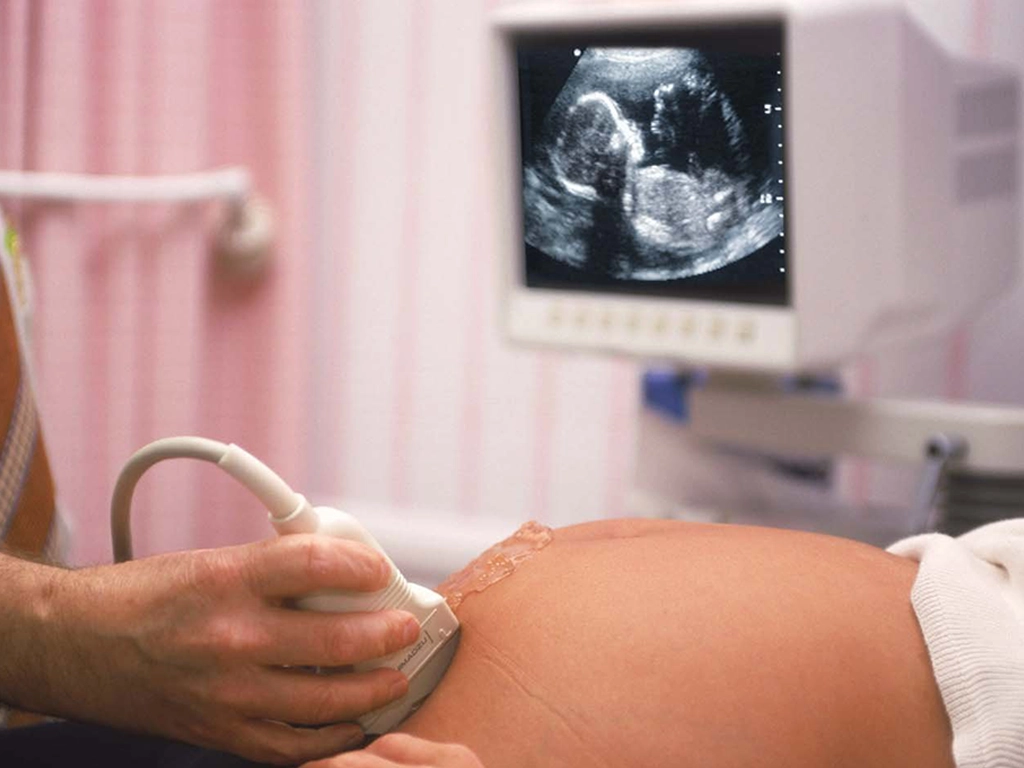

Theย Anomaly Scan, also known as the 20-week scan or anatomy scan, is a detailed ultrasound examination performed between 18 and 22 weeks of pregnancy to assess your babyโ€™s development and screen for structural abnormalities. This comprehensive scan evaluates the fetal brain, spine, heart, face, kidneys, limbs, and abdominal organs, as well as the placenta, amniotic fluid, and umbilical cord, to ensure proper growth and well-being. It is designed to detect a wide range of congenital conditionsโ€”including neural tube defects, heart anomalies, cleft lip, and skeletal dysplasiasโ€”while also providing important measurements to monitor fetal growth. If any concerns are identified, further counseling and diagnostic steps are offered to support informed decision-making for your pregnancy.